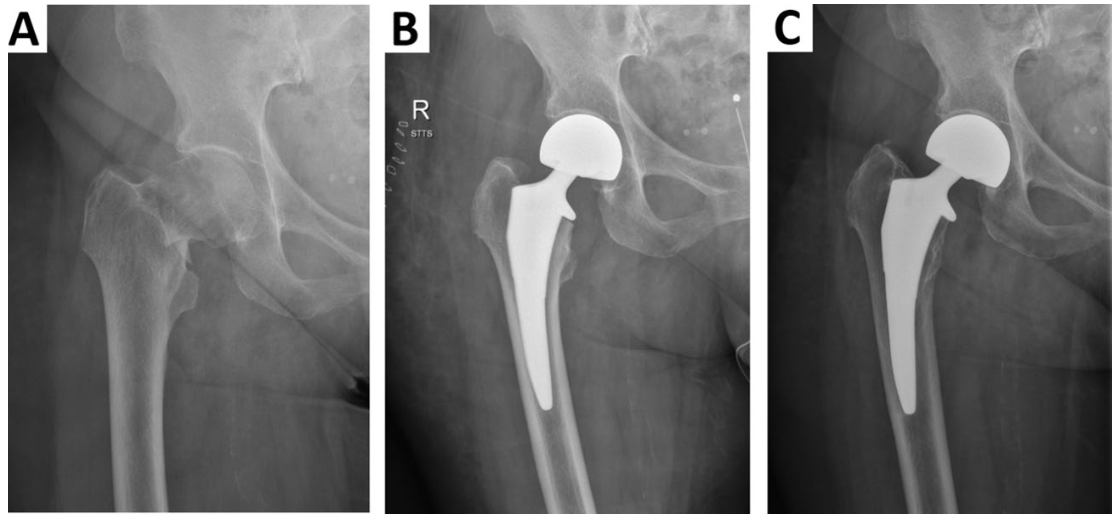

予約の患者さんの診療が13時過ぎに終わったので, 待機していただいた殿部痛の患者さんの診療を行いました. 股関節を動かすと痛みがあるので, 大腿骨頚部骨折と診断して, X線写真を撮像しました. その結果, 予想通り, 大腿骨頚部骨折でした. 非転位型だったので, 保存療法もできなくはなかったのですが, 超高齢であることから, 早期に離床, 歩行が可能となる人工骨頭挿入術を勧めました.

明日の午後, 予定していた手術が1件中止になったため, 明日の午後に手術を予定しました. 入院のオーダーや全身麻酔前の検査オーダー, 手術部との交渉, 麻酔科の医師への連絡等で, 15時過ぎまでかかりました.

この間に, 明日手術することになった大腿骨近位部骨折の患者さんとご家族に, 手術と輸血の説明を行いました.